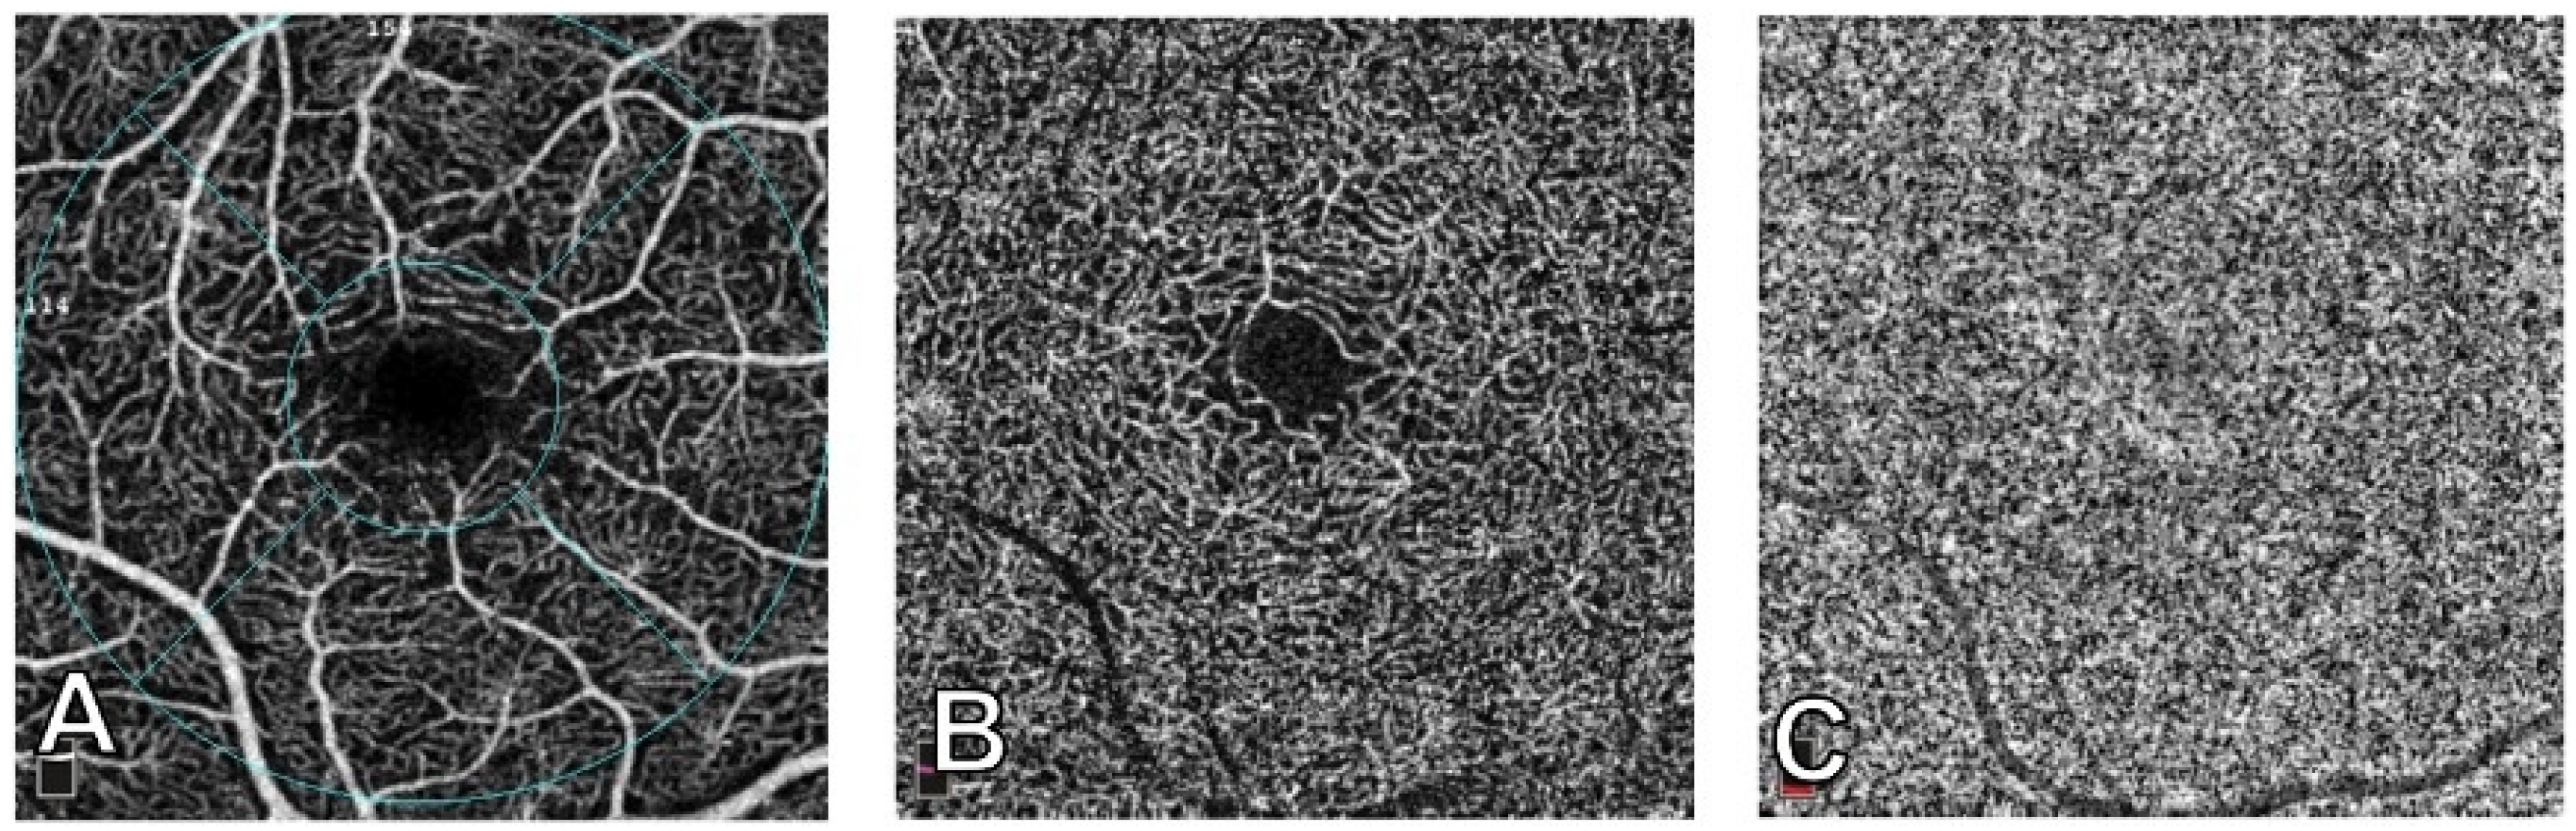

2.5. Indocyanine Green Angiography (ICGA)

2.6. Spectral Domain Optical Coherence Tomography (SDOCT)

2.7. Near-Infrared Reflectance (NIR)